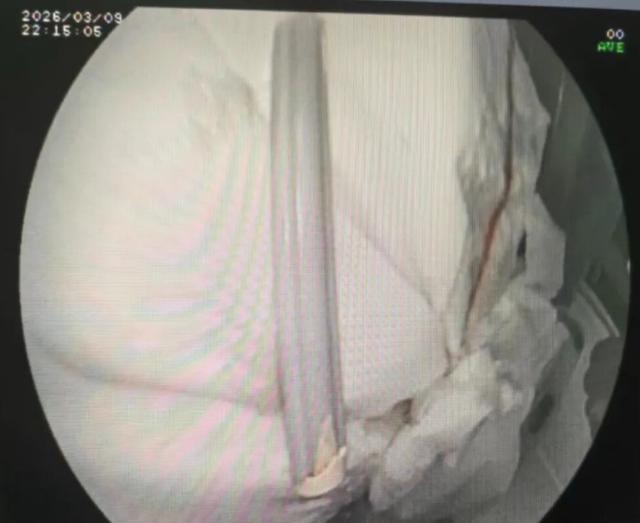

术中,在内镜视野下可见牙刷质地坚硬、表面光滑,长度约20厘米,抓取与取出难度较大。

经验丰富的胃镜室王美医师与洪艳护师沉着冷静,精准操控内镜器械,稳妥固定牙刷一端,小心翼翼顺着消化道生理弧度缓慢牵引。全程避开黏膜脆弱区域,防止划伤与穿孔,最终用时仅约五分钟,便将牙刷顺利经口腔取出。